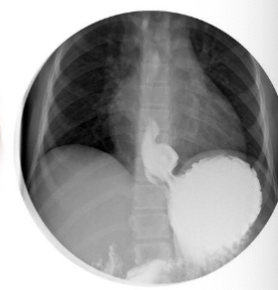

What is this

Hiatal hernia